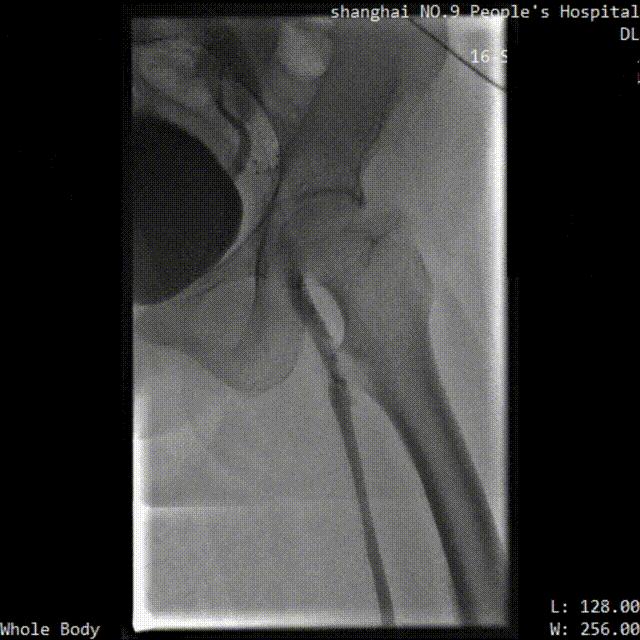

※ LuVoCaptor取栓前后管腔造影对照:

取栓术前管腔造影

取栓术后管腔造影